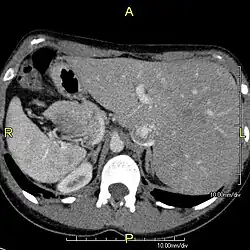

Diagnosis of situs inversus can be made using imaging techniques such as x-ray, ultrasound, CT scan, and magnetic resonance imaging (MRI).[9]

The condition affects all major structures within the thorax and abdomen. Generally, the organs are simply transposed through the sagittal plane. The heart is located on the right side of the thorax, the stomach and spleen on the right side of the abdomen and the liver and gall bladder on the left side. The heart's normal right atrium occurs on the left, and the left atrium is on the right. The lung anatomy is reversed and the left lung has three lobes while the right lung has two lobes. The intestines and other internal structures are also reversed from the normal, and the blood vessels, nerves, and lymphatics are also transposed.